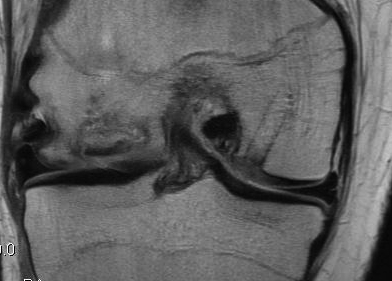

Insert dilator

Insertion device

- place over drill hole

- impact with hammer to seat in cartilage

- insert plug

- use tap to insert plug

- best to countersink 1 - 2 mm

Repeat